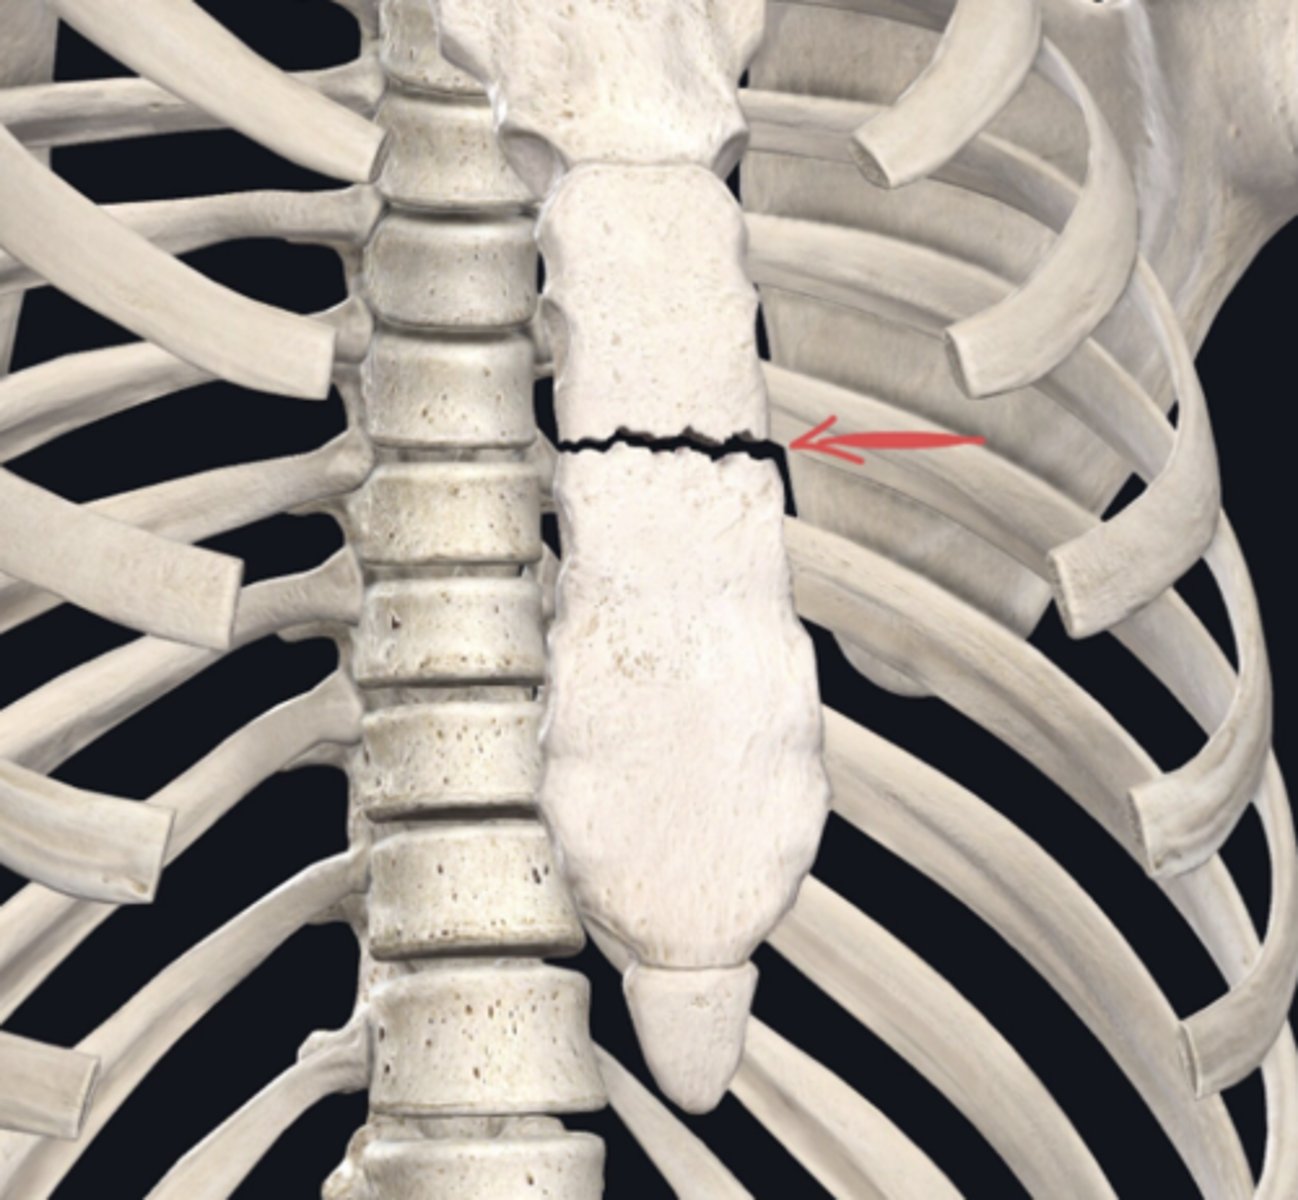

Transverse

(Note: Horizontal or axial would also be correct. Exam soft used in School ofMedicine only recognizes one correct answer, so if you answered either of these, the program may initially mark you wrong; your score would have to be corrected after the fact. For this reason, we encourage you to use the preferred term, listed first on the list of bold terms in your manual, and to spell it correctly!)

Identify the plane of section in which the indicated fracture has occurred. (Free response)